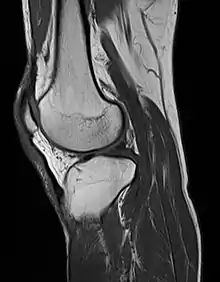

MRI of the knee

MRI uses strong magnetic fields to align atomic nuclei (usually hydrogen protons) within body tissues, then uses a radio signal to disturb the axis of rotation of these nuclei and observes the radio frequency signal generated as the nuclei return to their baseline states.[10] The radio signals are collected by small antennae, called coils, placed near the area of interest. An advantage of MRI is its ability to produce images in axial, coronal, sagittal and multiple oblique planes with equal ease. MRI scans give the best soft tissue contrast of all the imaging modalities. With advances in scanning speed and spatial resolution, and improvements in computer 3D algorithms and hardware, MRI has become an important tool in musculoskeletal radiology and neuroradiology.

One disadvantage is the patient has to hold still for long periods of time in a noisy, cramped space while the imaging is performed. Claustrophobia (fear of closed spaces) severe enough to terminate the MRI exam is reported in up to 5% of patients. Recent improvements in magnet design including stronger magnetic fields (3 teslas), shortening exam times, wider, shorter magnet bores and more open magnet designs, have brought some relief for claustrophobic patients. However, for magnets with equivalent field strengths, there is often a trade-off between image quality and open design. MRI has great benefit in imaging the brain, spine, and musculoskeletal system. The use of MRI is currently contraindicated for patients with pacemakers, cochlear implants, some indwelling medication pumps, certain types of cerebral aneurysm clips, metal fragments in the eyes and some metallic hardware due to the powerful magnetic fields and strong fluctuating radio signals to which the body is exposed. Areas of potential advancement include functional imaging, cardiovascular MRI, and MRI-guided therapy.